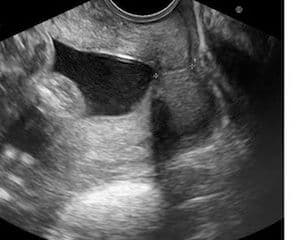

Over the last decades much research has been done on the etiology of premature deliveries, especially the relationship between cervical length and premature births. There is a reverse direct relationship between cervical length and the risk of premature births.

The Positive Predictive Value of Cervical Length Measurements by Transvaginal Ultrasound and the Risk of Delivery <35 weeks

Source: Iams NEJM 334, 1976